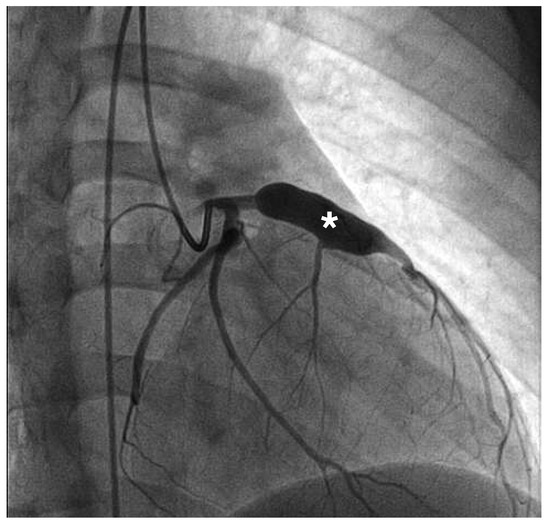

The patient was discharged with combined therapy of aspirin 100 mg/d and oral anticoagulation (international normalised ratio [INR]: 2–3). Coronary angiography six months later, showed partial remodelling with persistence of the LAD aneurysm (Figure 4). He underwent an exercise treadmill test nine months after disease onset. He achieved 92% of the maximum predicted heart rate without symptoms. The absence of ischaemia was confirmed with a positron emission tomography (PET) CT at the one-year follow-up.

Figure 4.

Coronary angiography with partial remodelling six months later. Only the left anterior descending artery aneurysm (*) persists.